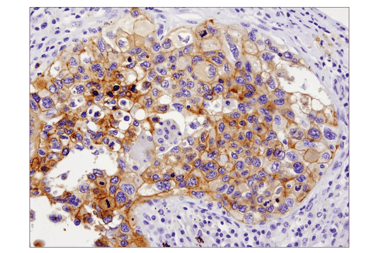

As tumor cells enter and travel through the bloodstream, they remain closely linked to an immunosuppressive microenvironment that helps them evade immune detection and clearance. Tumor cells and CAFs secrete factors such as CSF (G‑CSF), MCP‑1 (CCL2), IL‑6, IL‑1β, and CXCL12 (SDF1) to recruit myeloid‑derived suppressor cells (MDSCs) and tumor‑promoting M2 macrophages, often marked by CD163 and CD206.

MDSCs and M2 macrophages release immunosuppressive mediators, including Arginase‑1, IL‑10, and PD‑L1, which dampen cytotoxic T cell responses and protect associated tumor aggregates during intravasation and circulation. This immunosuppressive population functions as a mobile shield that accompanies clusters of circulating tumor cells, increasing their chances of surviving immune attack in the bloodstream.

![]() |

| IHC analysis of paraffin-embedded human colon adenocarcinoma using Arginase-1 (D4E3M™) Rabbit Monoclonal Antibody #93668 performed on the Leica BOND RX. | IHC analysis of paraffin-embedded human non-small cell lung carcinoma using PD-L1 (E1L3N®) Rabbit Monoclonal Antibody #13684 performed on the Leica BOND RX. |